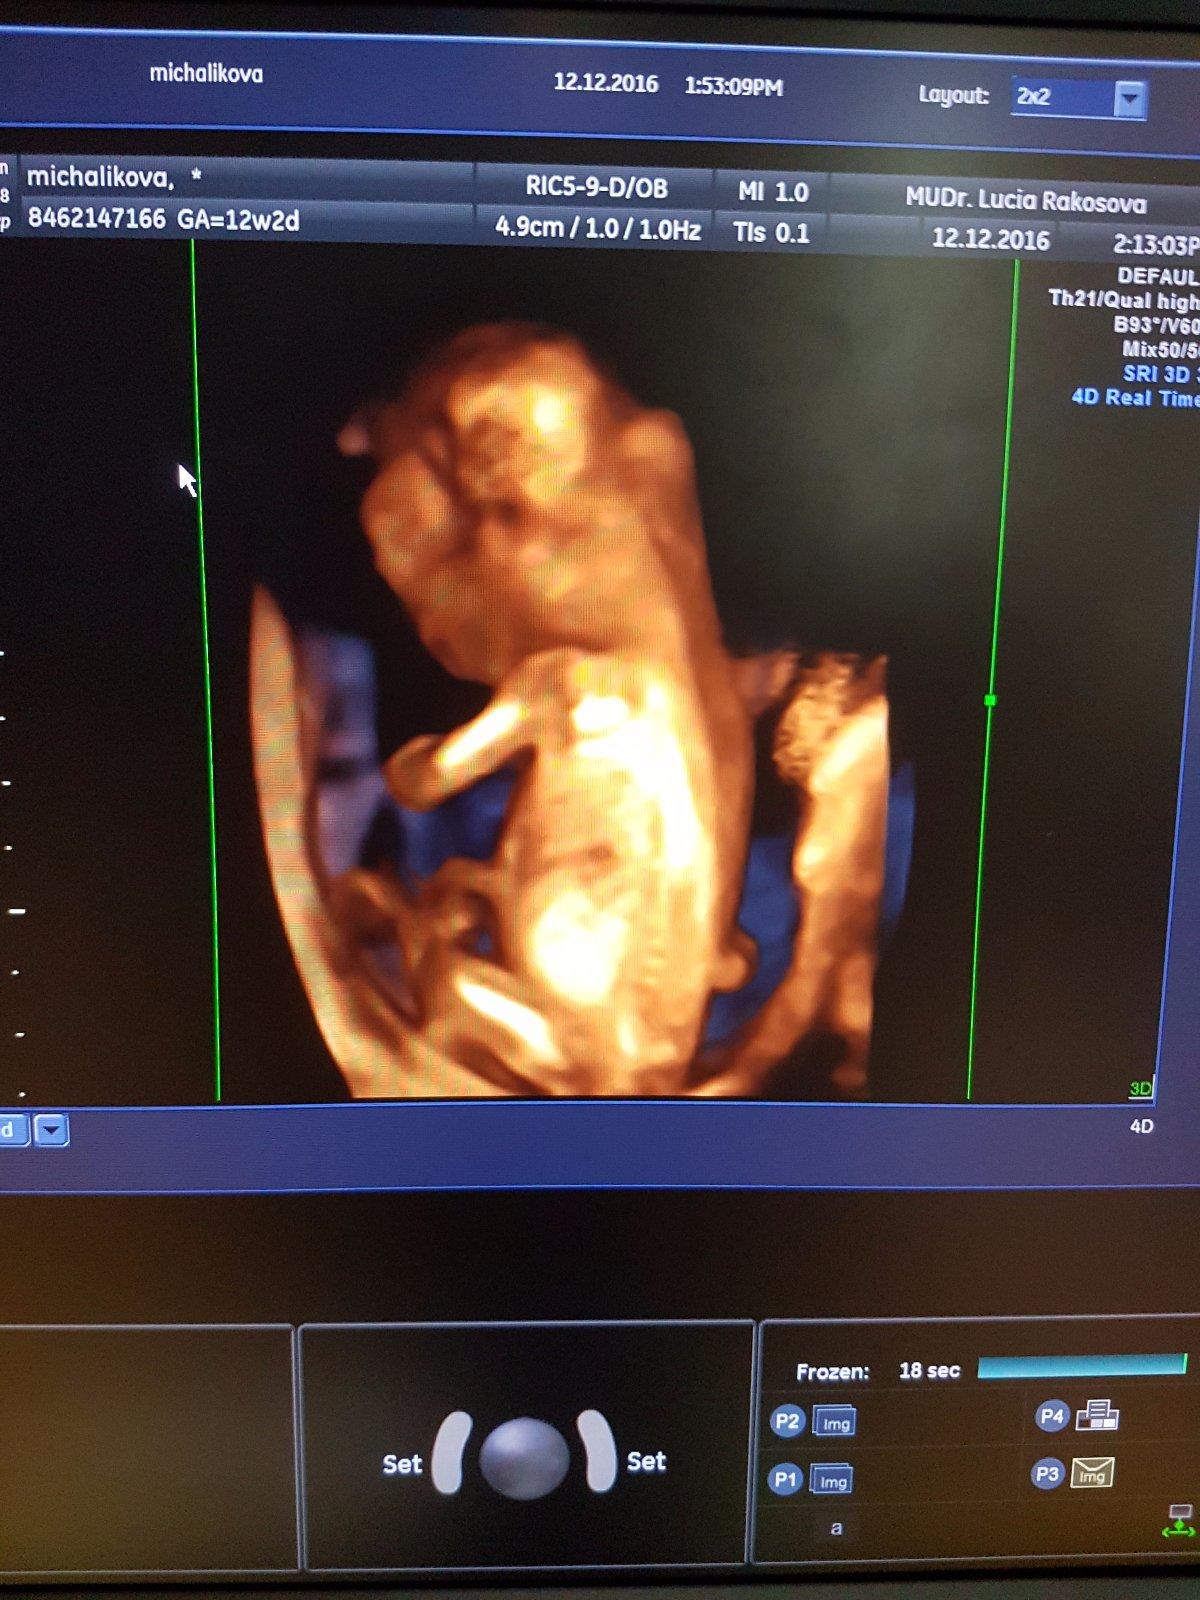

@renimac ahoj moja tak ako sa mate? Mne to uz pomaly ustupuje ale vecer mam take tlaky ale uz nezvraciam. Dnes idem na to 4d sono tak som zvedava ci mi povie pohlavie 🙂

@renimac moja tak uz som doma a ani za svet sa nechcelo ukazat v kuse sa tocilo chrbatikom a raz sa otocilo a ptekrizilo nozicky.normalne si z nas robilo dobry den 🙂 ale vse je ok

@renimac mne az odlahlo , vsetko pomerala a hlavne je v poriadku. Sak to bude urcite baba robi drahoty 🙂)) ale tem pristup no neskutocny ja som taku uzastnu doktorku este nestretla . Ten pristup neskutocne ako mi vsetko vysvetlila nikde sa neponahlala fakt sa mi venovala maximalne. Ale uz sme zas podla pm 12/2 a podla sona som uz 13/2

@lucka8787 ach ani mi nehovor a ja som sa taak tesila ze sa nam nasa fazulka ukaze🙂) alr pekne sa s nami hrala doktorka ze no toto je ake akcne babatko , ze to uz dlhoo nevidela🙂 no najskor cez brusko kde som to uplne inak videla a kedze mi vsetko meral, zistovala tak potom az zospodu a to bolo uz naadherne vidiet🙂 ale asoon viem, ze je v poriadku, lieta si tam jak stihacka 🙂